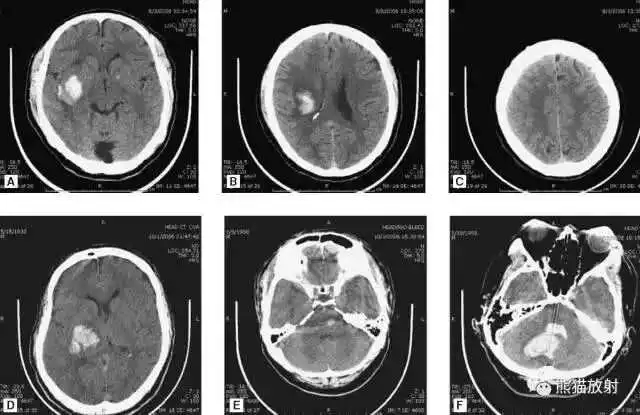

高血压性脑出血:

- 自发性出血;

- 继发于长期高血压及慢性血管病;

- 常见于基底节区、丘脑、脑桥、小脑。

A:占位效应,相邻脑沟、脑池消失;

F:脑出血破入四脑室。